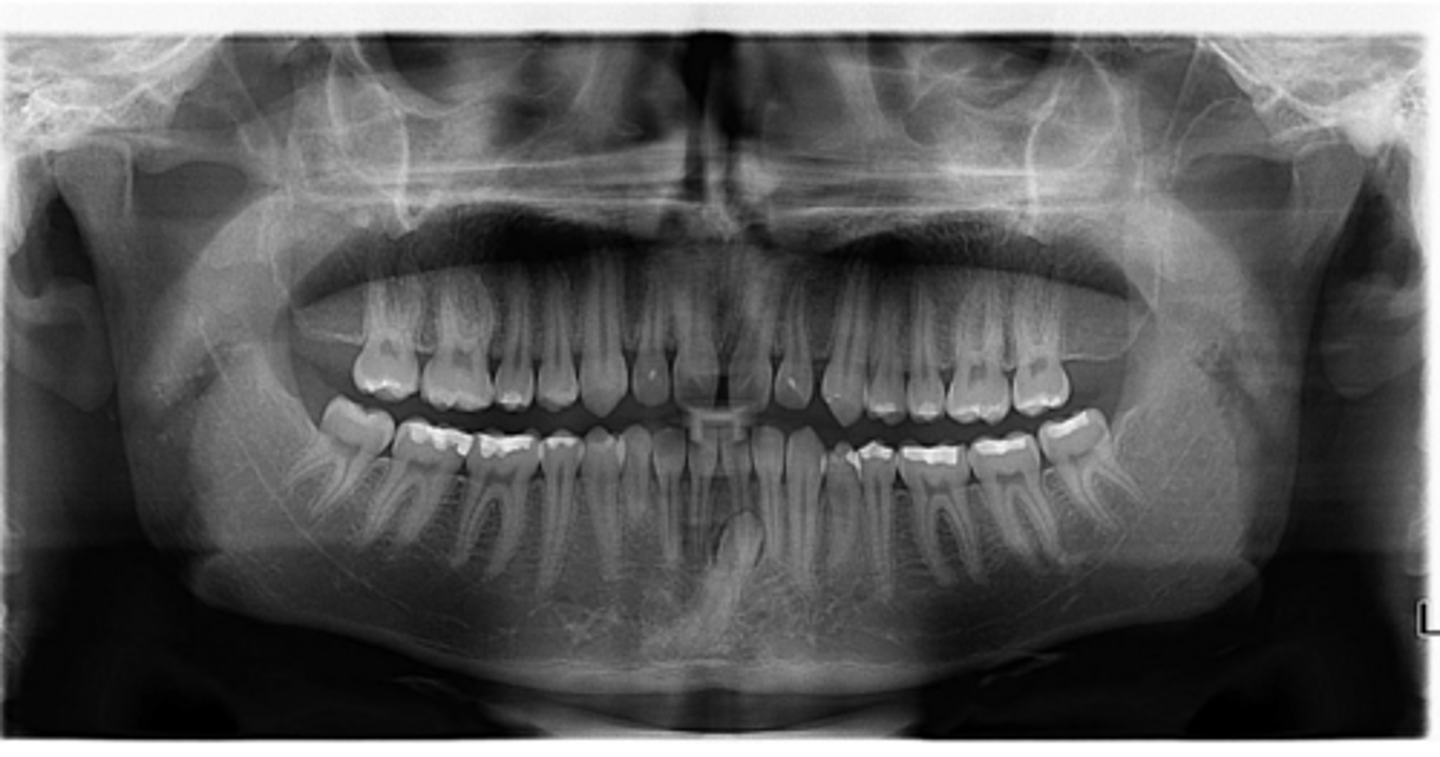

No

Are there congenitally missing teeth in the mandibular arch?

Are there congenitally missing teeth in the maxillary arch?

Are there any supernumerary teeth?

Are there retained primary teeth?

A little bit

Is there crowding?

Yes

Are the condyles symmetrical?

Is there any pathology?

Possibly #20

Are there any dilacerated roots?

Class II skeletal (very light)

What type of skeletal malocclusion is this patient?

Hypodivergent

Are the hyper-, hypo-, o normo- divergent?

proclined

Maxillary incisors are?

Class II

Hyperdivergent

Class I

Normodivergent

Are the maxillary incisors proclined/flared?